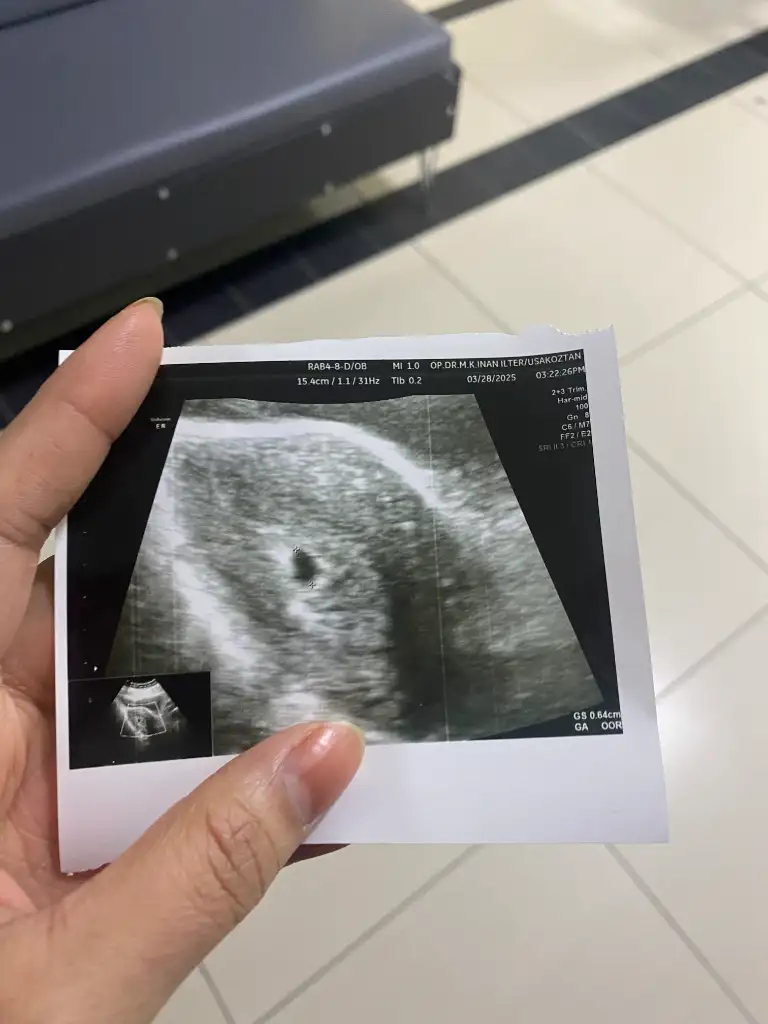

Görünürselam kızlar dün akşam 20.30 da beta baktırdım beta 3317 çıkmış bugün 5+0 olduk doktor kese için bugün çağırmıştı sizce keseyi görebilir miyiz.

Ya benimde bugün baktı 6 mm kese dedi çok mu küçük ben anlamadımKarnimdan canım

Ya benimde bugün baktı 6 mm kese dedi çok mu küçük ben anlamadım

Yok canım zaten Böyle oluyor ki. Benim ilk ultrasonda nokta gibiydi. Karın dan mı baktıYa benimde bugün baktı 6 mm kese dedi çok mu küçük ben anlamadım

Canım gayet normalYa benimde bugün baktı 6 mm kese dedi çok mu küçük ben anlamadım